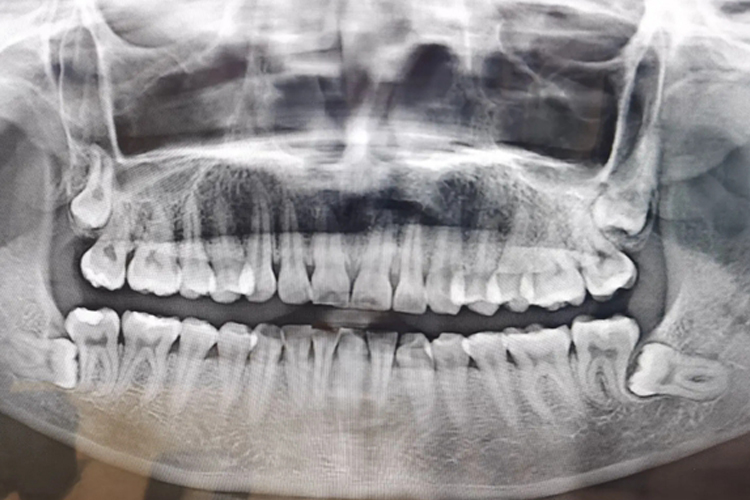

一般情况下,根据阻生智齿,即下颌第三磨牙在颌骨内的深度,可分为高位,中位及低位三类。

高位:对于高位阻生智齿,牙的最高部位平行或高于(牙合)平面。

中位:对于中位阻生智齿,牙的最高部位低于(牙合)平面,但高于第二磨牙的牙颈部。

低位:对于低位阻生智齿,牙的最高部位低于第二磨牙的牙颈部。对于骨埋伏阻生,即牙全部被包埋于骨内现象,也属于低位阻生智齿。